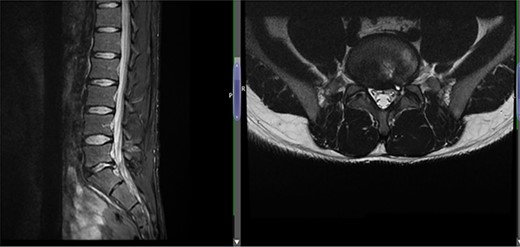

Case 1 L5-S1 level: there is disc desiccation and slight disc height loss; there is disc protrusion (including a cystic component) with impingement to the left traversing S1 nerve root.